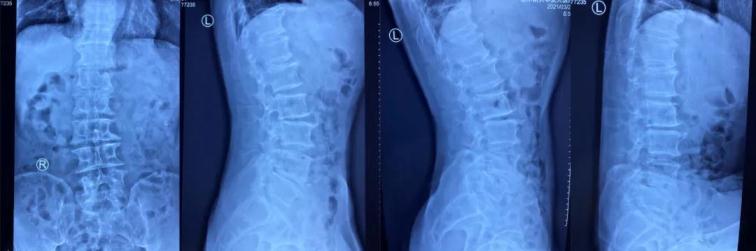

患者王某,男,65歲,腰痛伴右下肢麻痛1年,坐起及行走時(shí)疼痛明顯加重,行走不足100米即疼痛難忍需要休息,保守治療無效,嚴(yán)重影響生活質(zhì)量。慕名來到我院并找到喬院長(zhǎng)尋求治療?;颊呷朐汉?,經(jīng)過喬院長(zhǎng)認(rèn)真細(xì)致的檢查,診斷為:腰椎管狹窄、腰椎滑脫。

術(shù)前x線